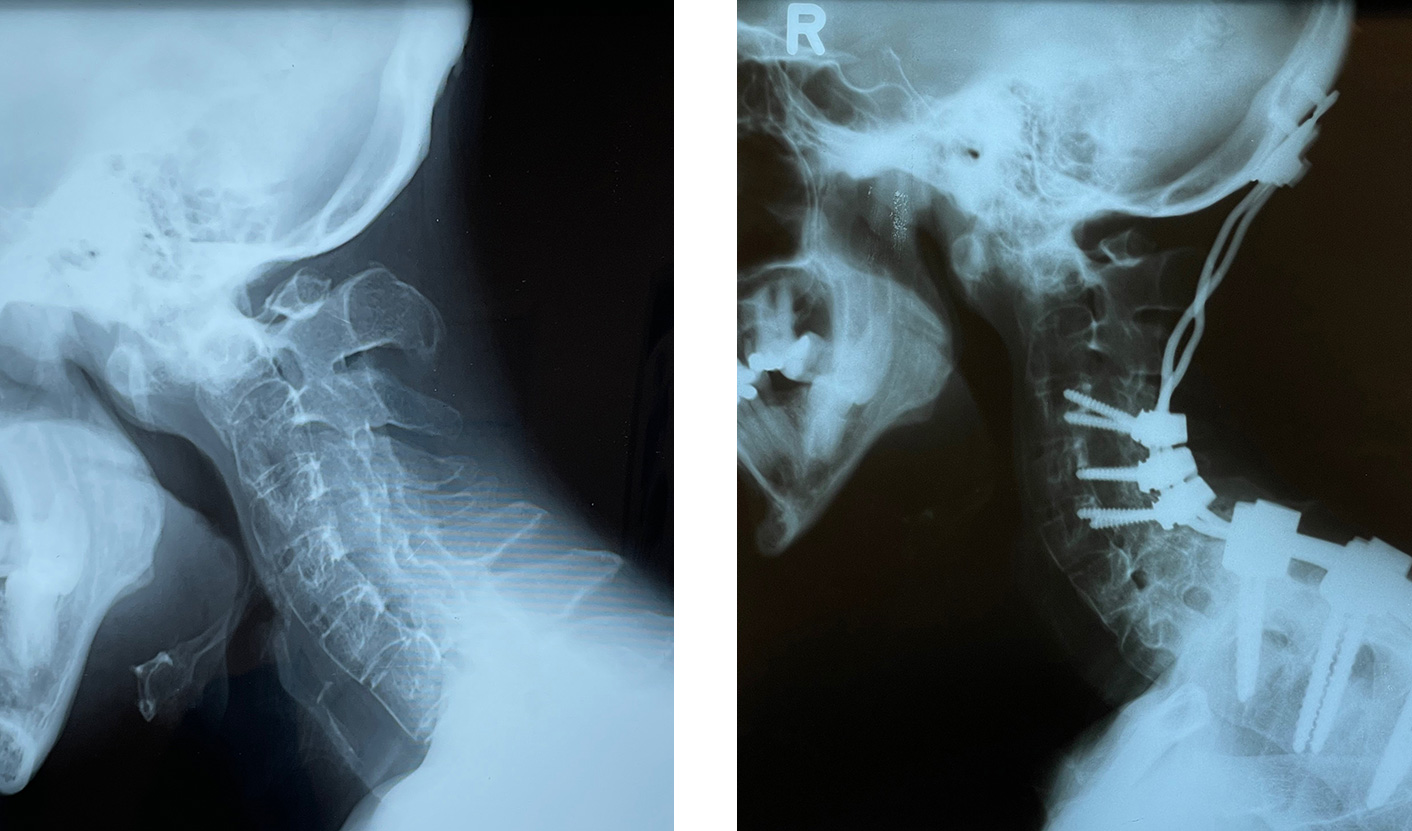

U ovoj fazi bolesti jedino lečenje je hirurško lečenje. Hirurškim putem se okoštali deo kičme u vratu razlabavljuje i mobiliše, a potom se u korigovanom ispravljenom položaju ponovo fiksira šrafovima i šipkama. Pacijenti ponovo dobijaju normalan uspravan stav tela i glave i time su ponovo sposobni da normalno žive i rade.

Slika istog pacijenta pre i odmah posle operacije, gde se vidi da nakon operacije može da gleda normalno pravo napred, što je pre operacije bilo nemoguće.

Pacijent i posle 13 godina živi potpuno normalno. Na intraoperativnom snimku se vide šrafovi, šipke i mesto gde je kičma kontrolisano „zalomljena“ i vraćena unazad, a potom u tom položaju fiksirana. RTG snimci pokazuju pogrbljenu kičmu i glavu pre operacije i urednu poziciju šarafova, pločica i šipki sa korigovanom pozicijom glave i vrata, nakon operacije.